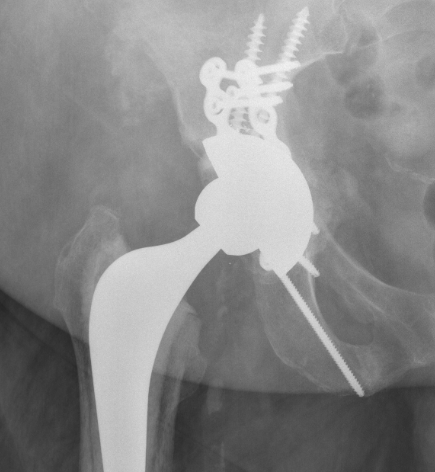

Intra-operative acetabular fracture

Postoperative acetabular fracture treated with double posterior plating

- plate posterior column if fractured

- screw fixation anterior column

- additional screws in cup +/- cage

- touch weight bear for period